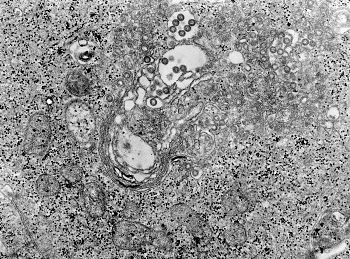

Crimean-Congo Hemorrhagic Fever (CCHF) Virus-viral particles (yellow) budding from the surface of cultured epithelial cells